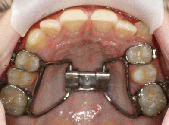

![]() | Zur schnellen Erweiterung des Oberkiefers eignet sich eine "Hyrax-Schraube", die fest an den Zähnen befestigt ist. |